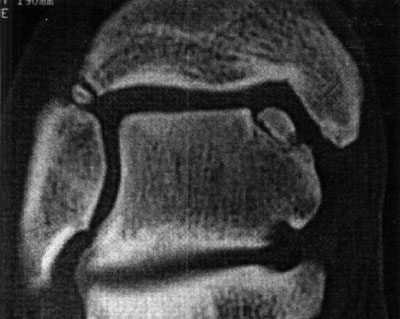

Foto 5: Lesión o.C. visualizada en RMN

La clasificación a partir de imágenes radiológicas mostró un coeficiente de correlación de Spearman de 0,77 (p=0,001) con respecto a la clasificación realizada a partir de imágenes tomográficas, en tanto que el mismo coeficiente entre las imágenes de TAC y RMN fue de 1 (p < 0,001). Esto implicaría una alta correlación entre la clasificación de TAC y RMN mientras que existiría una menor correlación entre Rx y TAC. En relación a los hallazgos de resonancia magnética, 12 pacientes (29,3 %) presentaron un GI, seis pacientes (14,6 %) presentaron un Gila, siete pacientes (17,1 %) un Glib, trece pacientes (31,7 %) un GIII y tres pacientes (7,31 %) un G IV. (fotos 6 a 10) Dieciocho pacientes (43,9%) fueron tratados en forma conservadora y 23 pacientes(56,1%0) fueron tratados en forma quirúrgica. (Ver tabla 4)

Foto 8: Lesión GII b

Foto 9: Lesión GIII

Foto 10: Lesión G IV